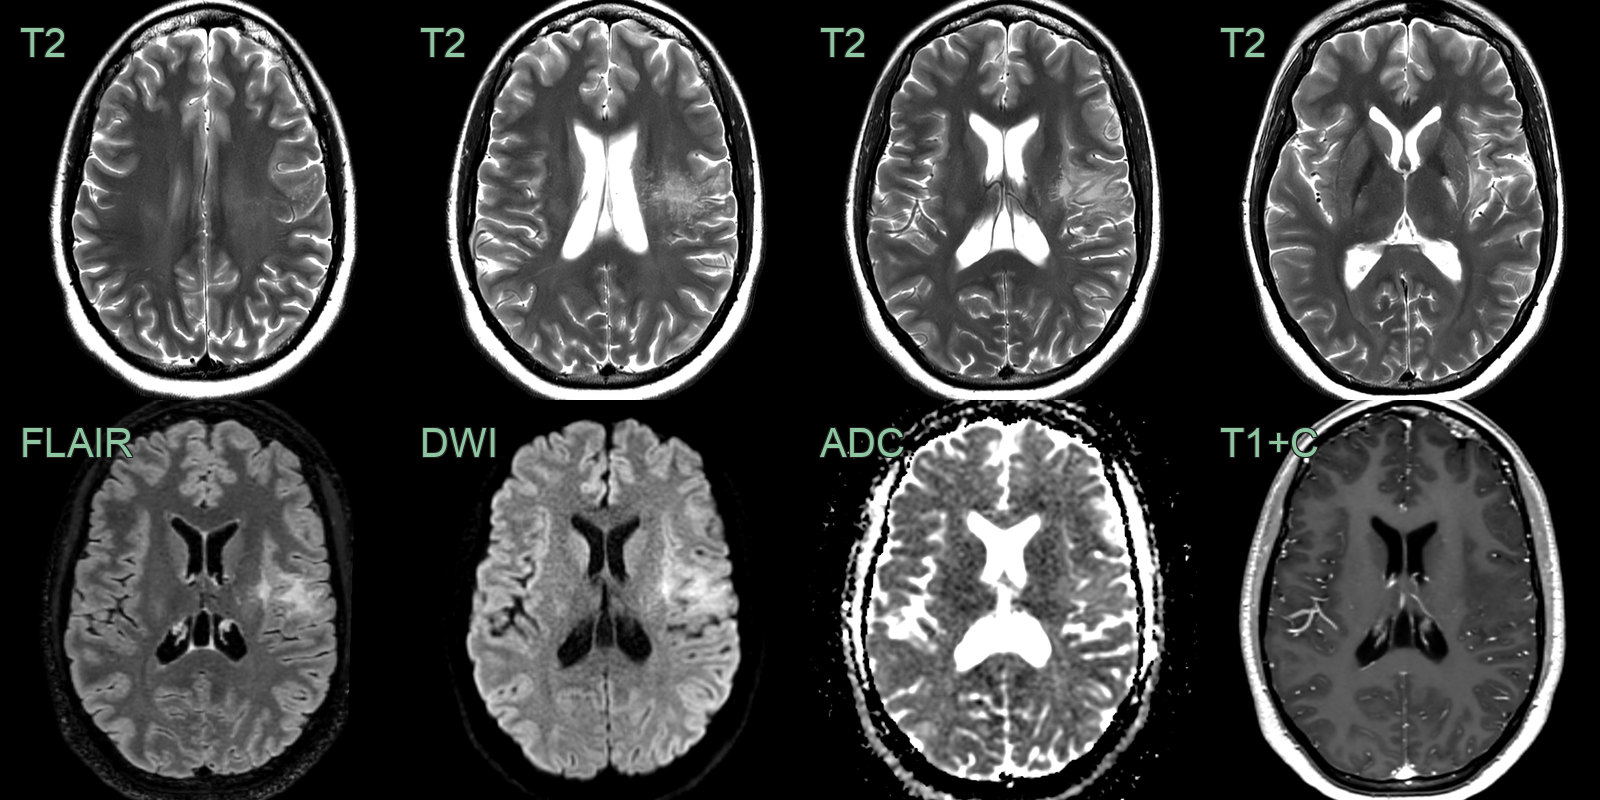

• On an MRI performed for headache, an incidental frontal lobe lesion was identified.

• The bubbly T2-hyperintensity and lack of enhancement are typical of MVNT,